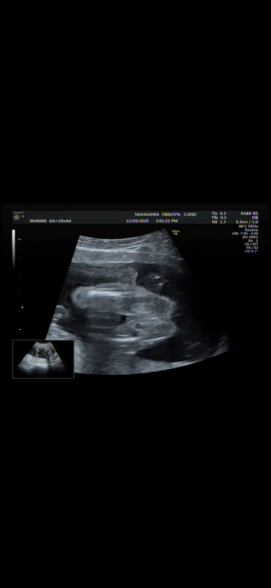

19週になりましたが、まだ性別がわかりません。 正月に家族とも話したいなーと思っているのですが 次の検診が年明けなので もし分かるのであれば教えて欲しいです!

へその緒が近くにあるのでわかりづらく、、

確定はできないのはわかっていますが多分どっちかでも知りたいです、、!

お腹の赤ちゃんの性別についてですね。

添付をしてくださった画像を拝見いたしました。

男の子のシンボルとなりそうなものがありそうに見えあたり、なさそうにも見えたりと、どちらかということもお返事がしにくい状況でした。